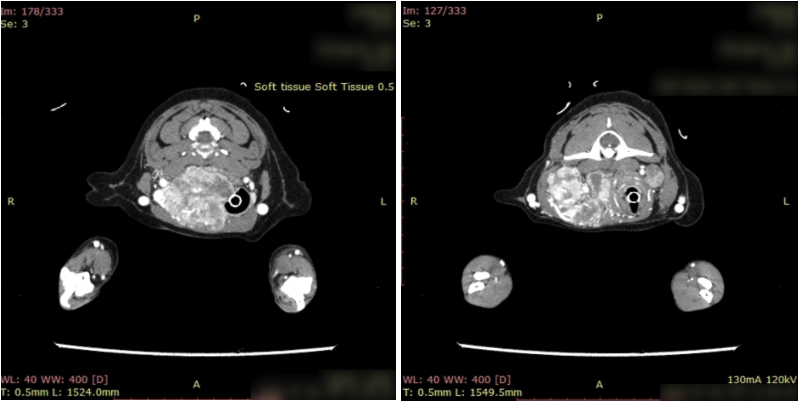

CT 검사 및 세침흡인 검사를 진행한 결과, 갑상선 유래 종양이 의심된다는 소견을 받았습니다. 갑상선 종양은 본래 수술이 1순위로 고려되나, CT상 경동맥, 경정맥, 주변 신경 등 주변 조직에 침습되어있어 수술 위험도 높아 방사선 치료로 선택하였습니다.

강아지 갑상선 환자의 CT 검사 결과 / 출처: 에스동물암센터